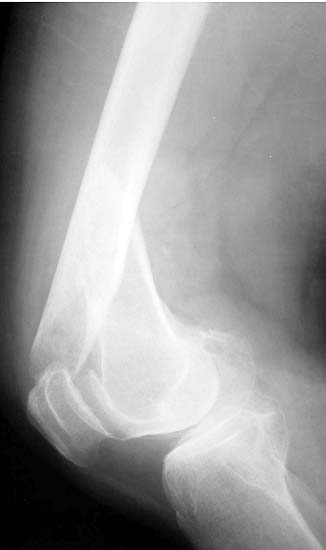

股骨远端骨折是指股骨下端15cm以内的骨折。随着交通运输和工农业的发展,由高能量暴力造成的该部为骨折有增多的趋势,而且伤情复杂,并发症多、致残率高,是难治的骨折之一。股骨远端骨折多位与髓腔狭窄不易下,以髓内钉为基础的中心型固定方法更符和股骨的生物力学特点,固定确实,且不破坏骨折短的血运,便于患肢尽早活动,被称为“生物学”内固定技术。可以达到满意的复位,恢复关界面与关节间的正常解剖关系。,采用这种可靠稳妥的固定技术,便于早期进行膝关节的CPM练习,缩短骨折愈合时间,降低骨不愈合率及感染率。最大限度减少膝关节僵硬、粘连及畸形等并发症是治疗的关键所在。

股骨远端粉碎骨折 采用闭合逆行穿钉法,带锁髓内钉内固定